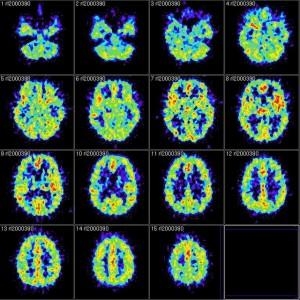

Gli esami neuroradiologici sono eseguiti con risonanza magnetica, spettroscopia, trattografia e risonanza funzionale per definizione del volume tumorale pre e post-operatorio e valutazione della risposta alle terapie (radio e chemioterapia), in collaborazione con i medici della Neuroradiologia. La strumentazione endoscopica è di ultima generazione, con ottiche dedicate alla chirurgia ipofisaria, telecamera a 3 CCD (sensori ottici), sistema integrato di visualizzazione di immagini e registrazione (Brain Suite).